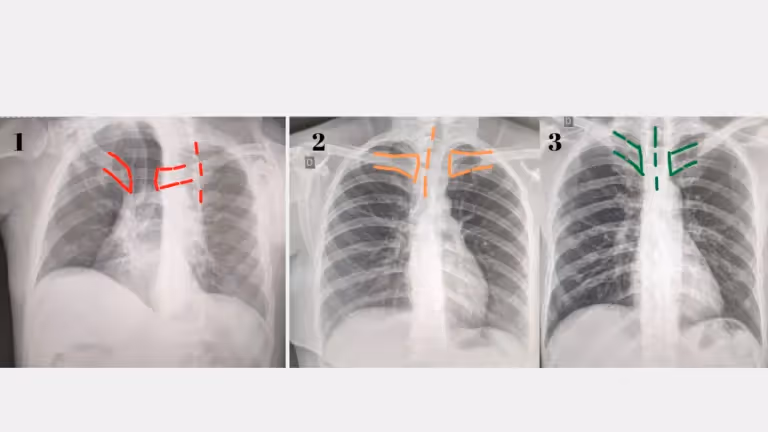

- Alinhamento: refere-se à posição correta do objeto e do equipamento de radiografia durante o exame. O alinhamento incorreto pode resultar em uma imagem borrada, obscurecida ou distorcida. No raio-x de tórax, usa-se a distância das clavículas ao processo espinhoso da coluna vertebral como parâmetro de alinhamento (devem ser equidistantes).